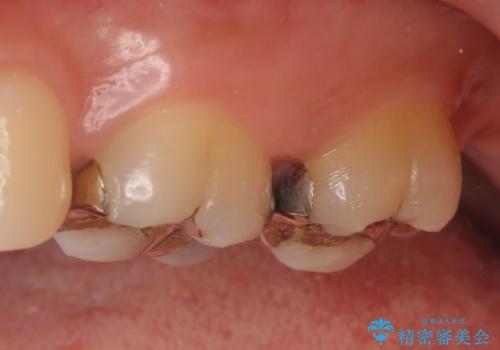

左上7近心の虫歯は歯茎より深く、歯茎を下げるため歯周外科を行いました。

術後歯肉の回復を待ち、左下6、7ともにセラミックインレーによる修復を行いました。